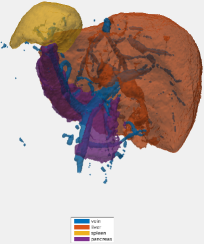

Training and validation: Our dataset includes 331 contrast-enhanced abdominal clinical CT images in the portal venous phase used for pre-operative planning in gastric surgery. Each CT volume consists of slices of pixels. The voxel dimensions are [0.59-0.98, 0.59-0.98, 0.5-1.0] mm. A random split of 281/50 patients is used for training and validating the network, i.e., determining when to stop training to avoid overfitting. In both training stages, we employ smooth B-spline deformations to both the image and label data, as proposed by Çiçek et al. (2016). The deformation fields are randomly sampled from a normal distribution with a standard derivation of 4 and a grid spacing of 32 voxels. Furthermore, we applied random rotations between and to the training images for plausible deformations during training. No deformations were applied during the testing. We trained 200,000 iterations in the first stage and 115,000 in the second. Table 1 summarizes the Dice similarity scores for each organ labeled in the 50 validation cases. On average, we achieved a 7.5% improvement in Dice scores per organ. Small, thin organs such as arteries especially benefit from our two-stage hierarchical approach. For example, the mean Dice score for arteries improved from 59.0 to 79.6% and from 54.8 to 63.1% for the pancreas. The effect is less pronounced for large organs, like the liver, the spleen, and the stomach. Fig. 3 shows an example result from the validation set and illustrates the tiling approach. The 3D U-Net separates the foreground organs well from the background tissue of the images.

Testing: Our test set is different from our training and validation data. It originates from a different hospital, scanner, and research study with gastric cancer patients. 150 abdominal CT scans were acquired in the portal venous phase. Each CT volume consists of slices of pixels. Voxel dimensions are [0.55-0.82, 0.55-0.82, 0.4-0.80] mm. The pancreas, liver, and spleen were semi-automatically delineated by three trained researchers and confirmed by a clinician. Figure 4 shows surface renderings for comparison of the different stages of the algorithm. A typical testing case in the first and second stages is shown using non-overlapping and overlapping tiles (Eq. 4). Dice similarity scores are listed in Table 2. This dataset provides slightly higher image quality than our training/validation dataset. Furthermore, its field of view is slightly more constrained to the upper abdomen. This probably explains the better performance for liver and pancreas compared to the validation set in Table 1.